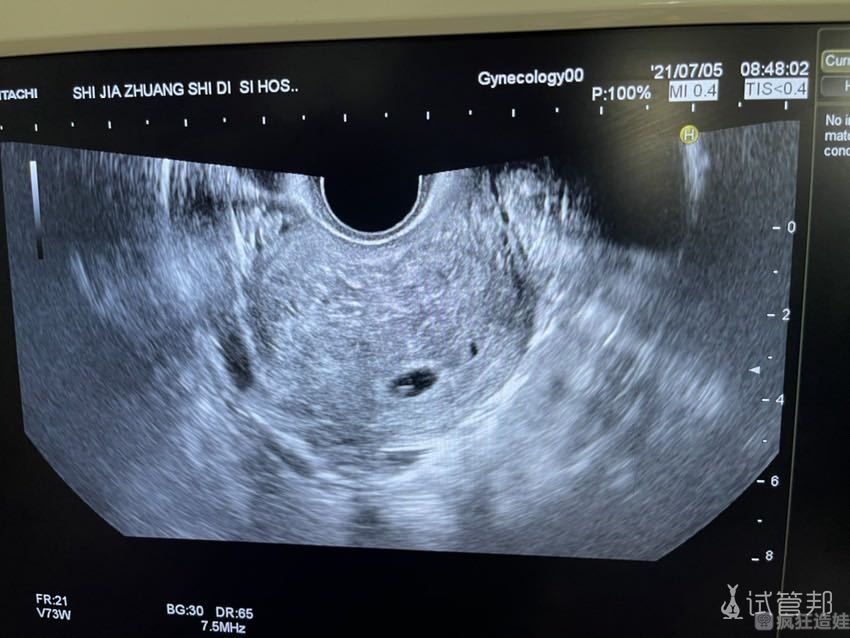

月经第二天打一针长效降调,28天再打第二针,打完针在角落哭了一会,去厕所整理一下就回去上班了。再过28天返院B超开始吃补佳乐、阿司匹林、二甲双胍、红花逍遥丸、双橘颗粒,12天后再B超说有宫腔分离、一边打黄体酮一边观察。3天后复查宫腔分离没有了,准备移植了。2020年7月3号移的,打了防宫缩的依保,躺了半小时离开去租住的小房子了。大部分时间躺着,吃完饭走动一下,不能吃的都禁嘴,吃滋肾育胎丸、二甲双胍、补佳乐、孕酮。第八天才敢洗头洗澡,每天看看唱歌类综艺节目,每天好难熬吃药打针躺着。无胸涨,就是尿频,小肚子针扎感抽痛感。又盼时间过快点,又担心结果难以承受,对于我而言好孕比孙悟空取经还要难...